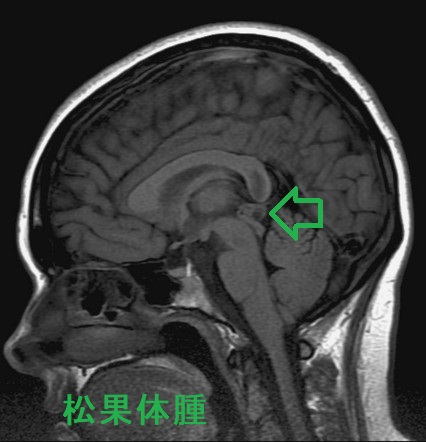

松果体部腫瘍の症状は

- 中脳水道狭窄による水頭症・頭蓋内圧亢進症状

- 視蓋前域の圧迫;眼球運動障害・上方注視麻痺、眼瞼下垂、瞳孔の対光反射・調節反射の消失(Parinaud症候群)

- 特に男児で視床下部の圧迫により思春期早発症

β-ヒト絨毛性ゴナドトロピン(hCG)、はα-フェトプロテイン(AFP)が上昇松果体腫・松果体芽腫は上昇しない

治療は外科的切除、術後放射線治療・抗がん剤治療